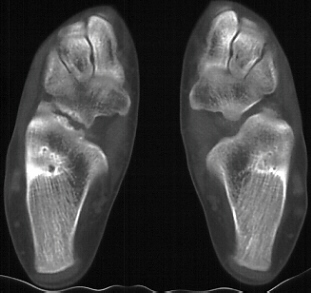

CT scan - Confirms the presence of a calcaneonavicular fibrous or

cartilaginous bar. TREATMENT: Conservative measures of shoe modification and activity restriction

Radiographs - AP, lateral, oblique at 45 degrees, and Harris view. A coalition may be difficult to pick up on the AP and lateral views due to the overlap of bones but there may be some subtle clues. Beaking of the talus or narrowing of the subtalar joint may be present. Calcaneonavicular bony bridges can be seen on the lateral view with the classic "anteater nose" coming from the calcaneous. Harris view may be helpful to evaluate the subtalar joint but a CT is often obtained to rule out subtalar coalition. The ankle may remodel to a ball and socket joint secondary to limited subtalar motion. Coronal CT cuts are most helpful in evaluating talocalcaneal bony bridges while transverse cuts are used for calcaneonavicular bars.